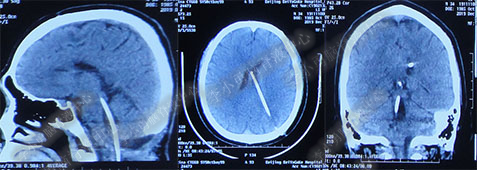

2016年5月9日因“间断性眩晕半月,恶心呕吐一周”以“梗阻性”脑积水,第1次住入北京某企业三级医院神经外科内镜组。2016年5月10日(入院后第2天)行头部MRI(图-1)检查示脑室系统扩张。

图-1:2016年5月10日头部MR